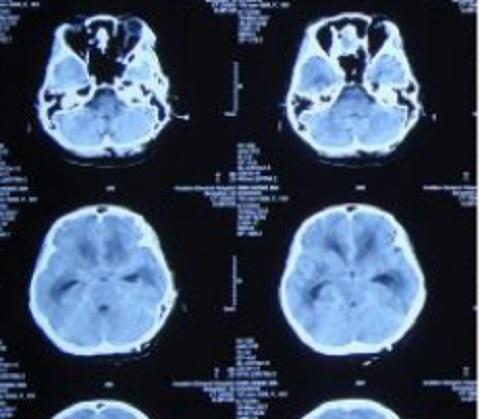

6月20日,引流脑脊液仍然色黄浑浊,复查头CT环池、鞍区仍然密度升高、间隙消失。

8月16日,患者脑脊液仍然色黄浑浊,复查增强MRI现实四叠体池区、鞍区、环池内多发结核脓肿。

10月18日,患者脑脊液外观基本清亮,增强头MRI现实仍然课件鞍区多发结核脓肿、四叠体池、环池内病变明显改善。

10月20日,行分流手术,术后复查增强头MRI见图。